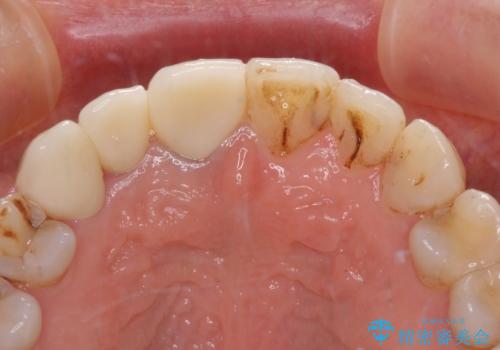

- 前歯の歯並びやむし歯治療の跡、奥歯の銀歯を気にして来院された患者様です。

インビザラインによる矯正治療の後に虫歯や銀歯をセラミックにて補綴することとしました。

前歯のむし歯治療の跡や奥歯の目立つ銀歯がなくなり、明るい口元になりました。